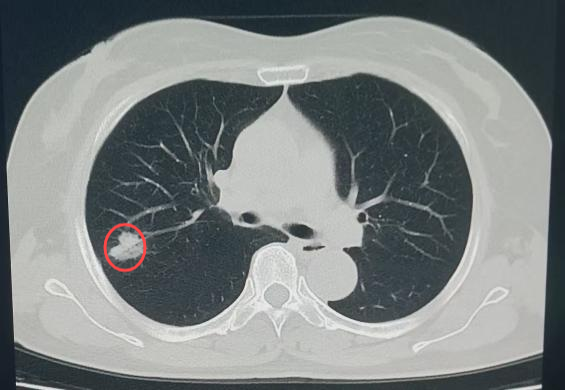

放射影像科在诊断过程中,借助AI肺结节筛查软件,敏锐捕捉到王女士右侧肺叶存在一个大小约17×22mm的部分实性结节。不仅如此,系统还迅速调取了她2023年在该院体检时的影像资料。影像科医生仔细比对后发现,虽然2023年王女士右肺叶的结节已存在且大小无明显变化,但结节的质地从磨玻璃样转变为少许实性的混合磨玻璃样,边界进一步清晰,边缘还出现了浅分叶及短毛刺等典型的恶性征象。与此同时,AI筛查软件也发出警示,将该结节的危险程度判定为“高危”。即便王女士自述并无任何呼吸系统症状,凭借专业的判断,影像科还是高度怀疑该结节存在肿瘤性病变的可能。

(2025年结节影)